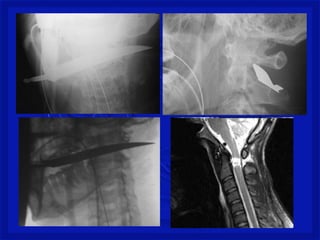

Registro fotográfico Pessoal

TRM – TraumatismoRaqui- Medular